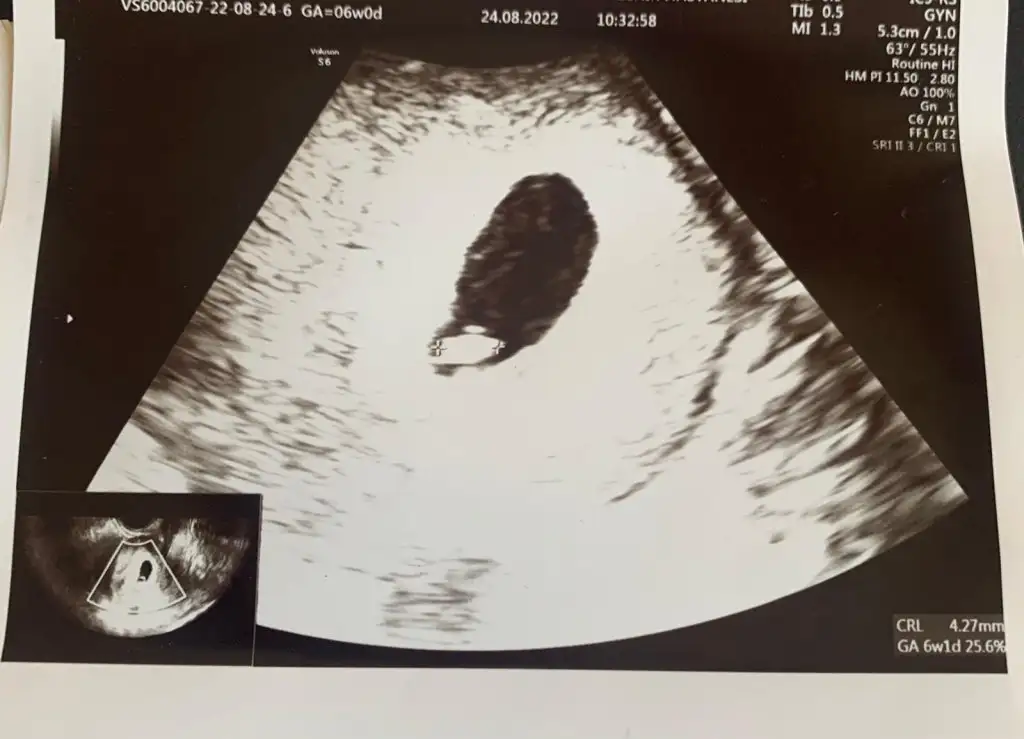

Bebek 4 mm 6+1 hafta ile uyumlukızlar benım ultrasona bakar mısınız . aşağıda sayılar falan yazıyor ndır onlar yardımcı olur musunuz